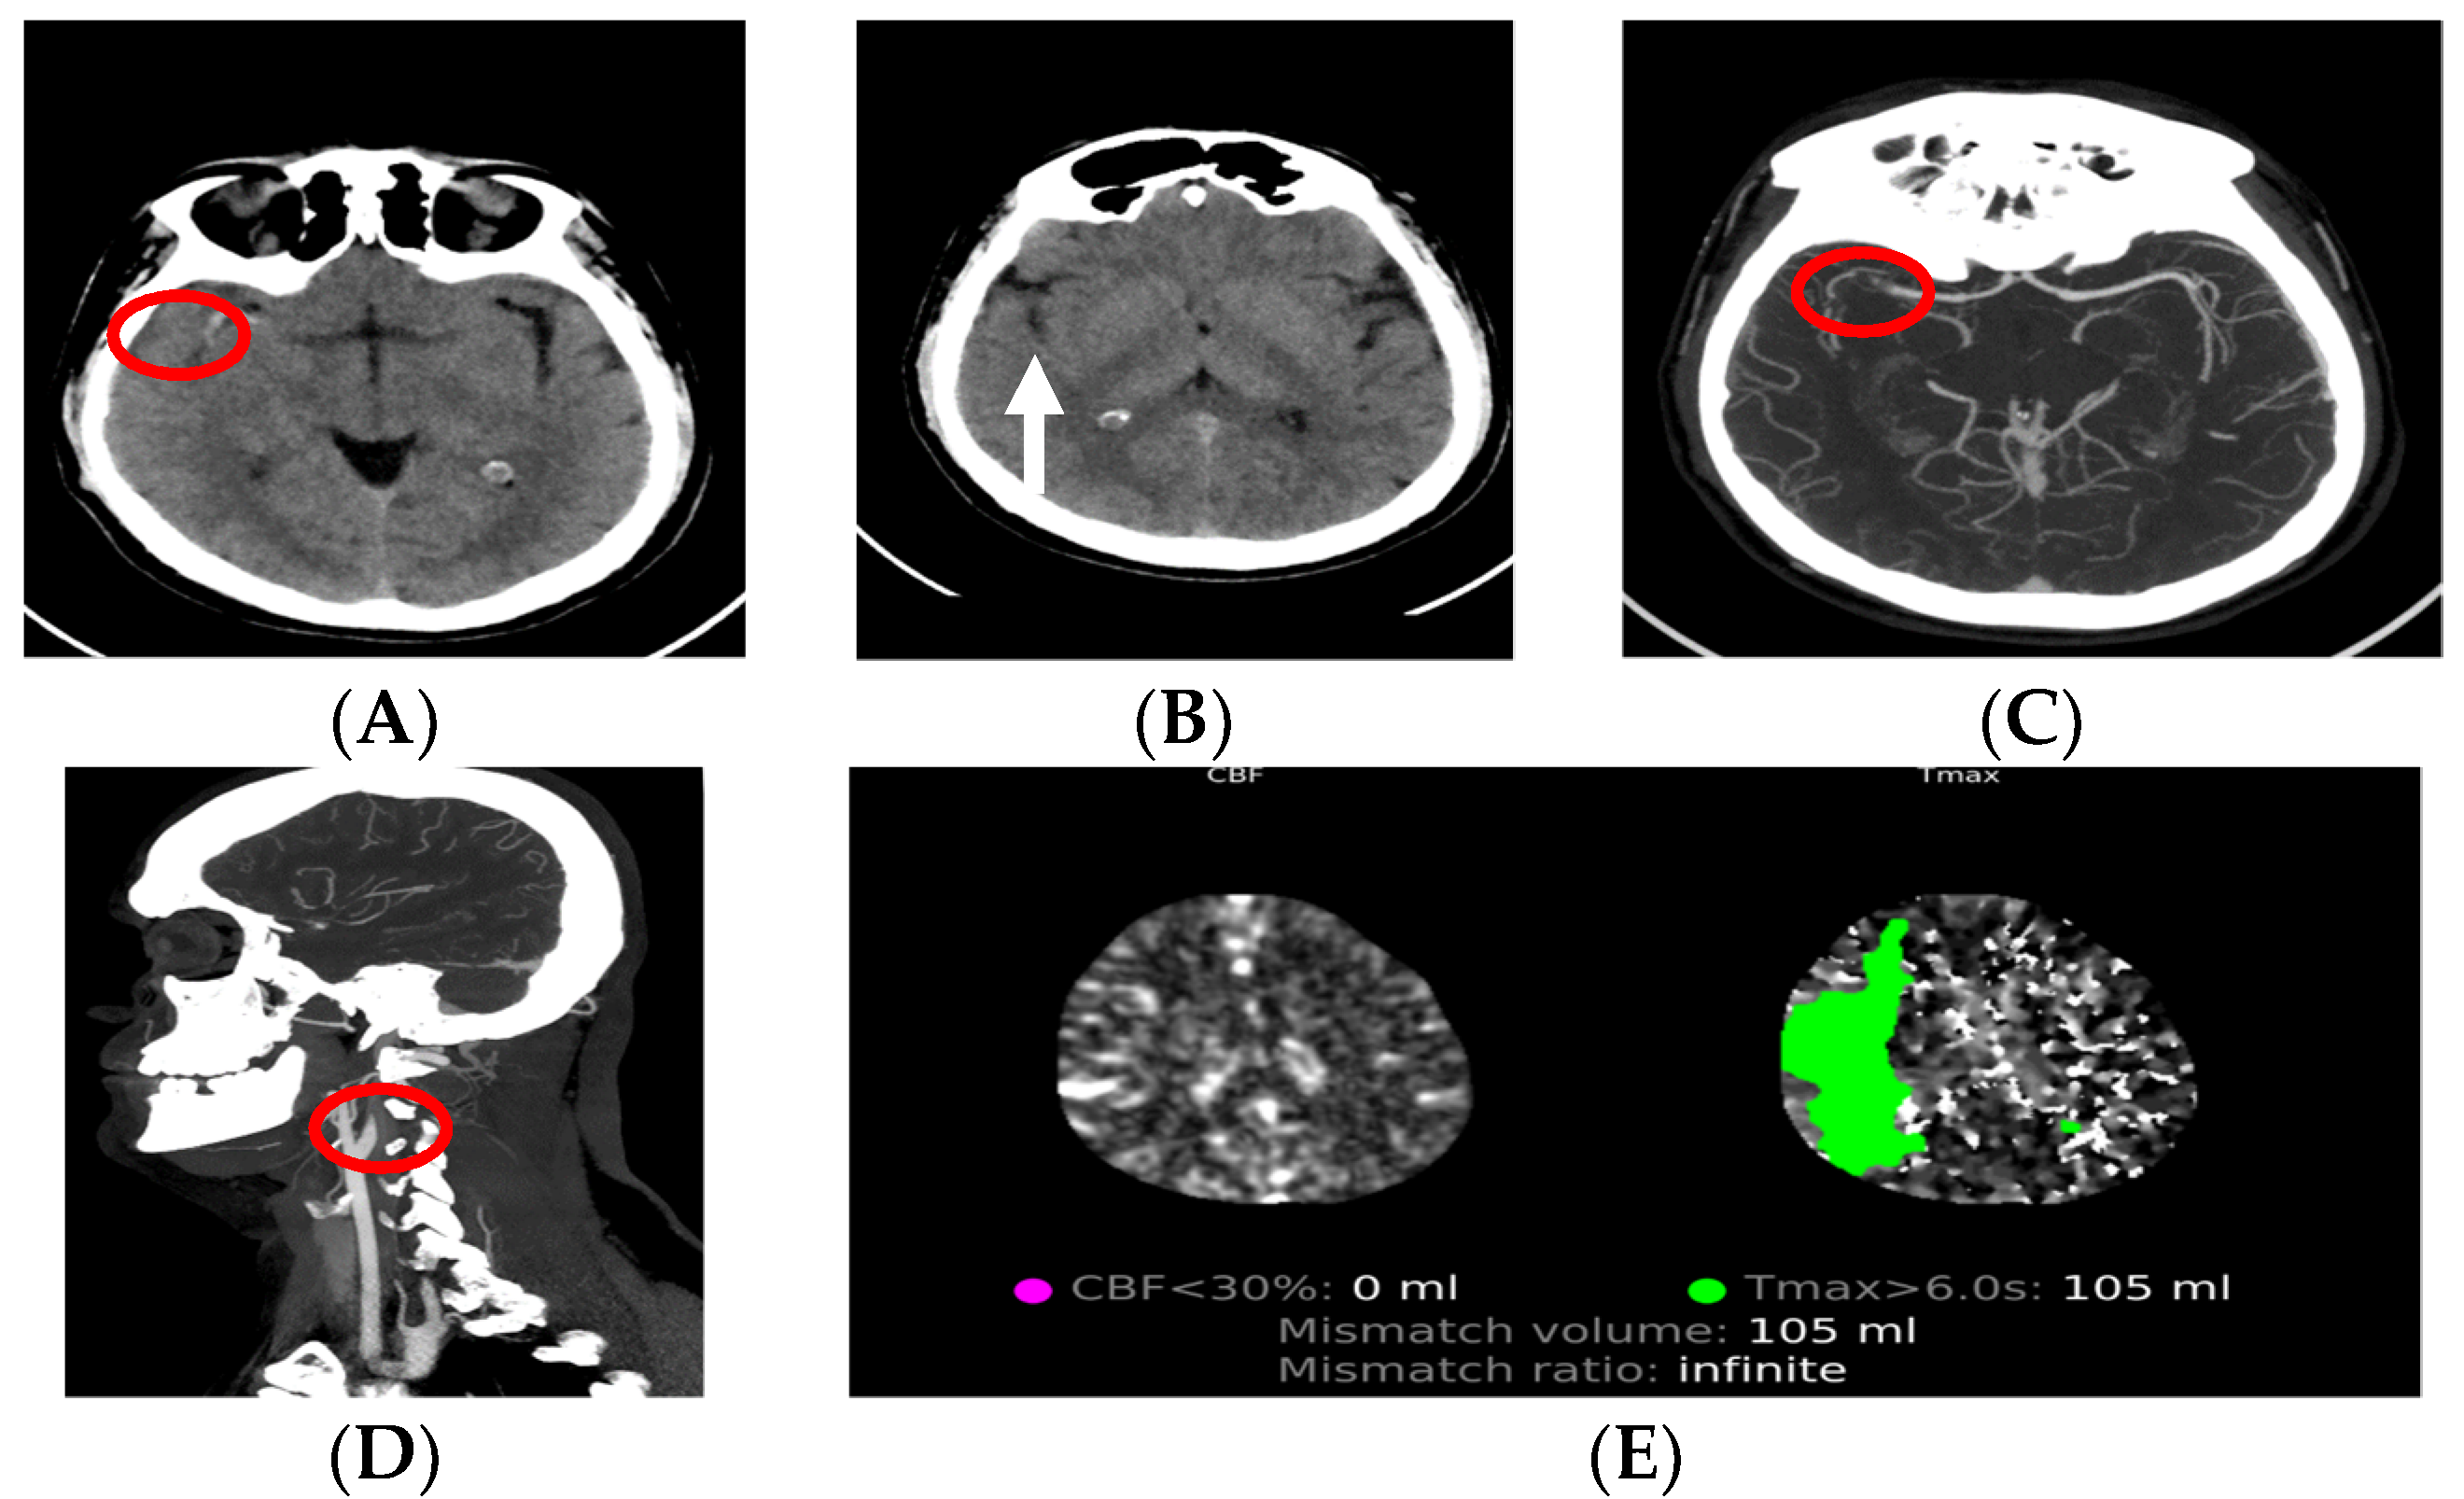

CT perfusion allows patients who are outside the time window for reperfusion therapy (>4.5 h for intravenous thrombolysis and >6 h for mechanical thrombectomy (MT)) to have the opportunity to receive treatment, if there is a penumbra area left that is viable [47,50]. Under the criteria for CT perfusion, an MT can be performed in patients with an infarct core of ≤70 mL and large vessel occlusion [36]. The use of CT, CT angiography and CT perfusion in daily practice (experience from the Stroke Center, AORN Cardarelli, Naples, Italy) is presented in Figure 2.

Figure 2. Patient, male, 48 years old, presented with left hemiplegia and dysarthria at the emergency department, after which a neurologist ordered CT diagnostics. (A,B) Non-contrast CT which shows MCA hyperdensity (red circle), loss of right insular ribbon (white arrow) and ASPECT 9. (C,D) CT angiography, axial and sagittal, showing tandem occlusion of origin of R-ICA (dissection) and R-MCA (both in red circles). (E) CT perfusion showing mismatch volume of 105 mL.